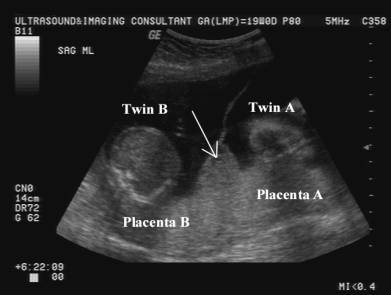

O “Sinal do Y ou λ (Lambda)” na ultrassonografia é indicativo de qual tipo de gestação Gemelar?

Dicoriônica.